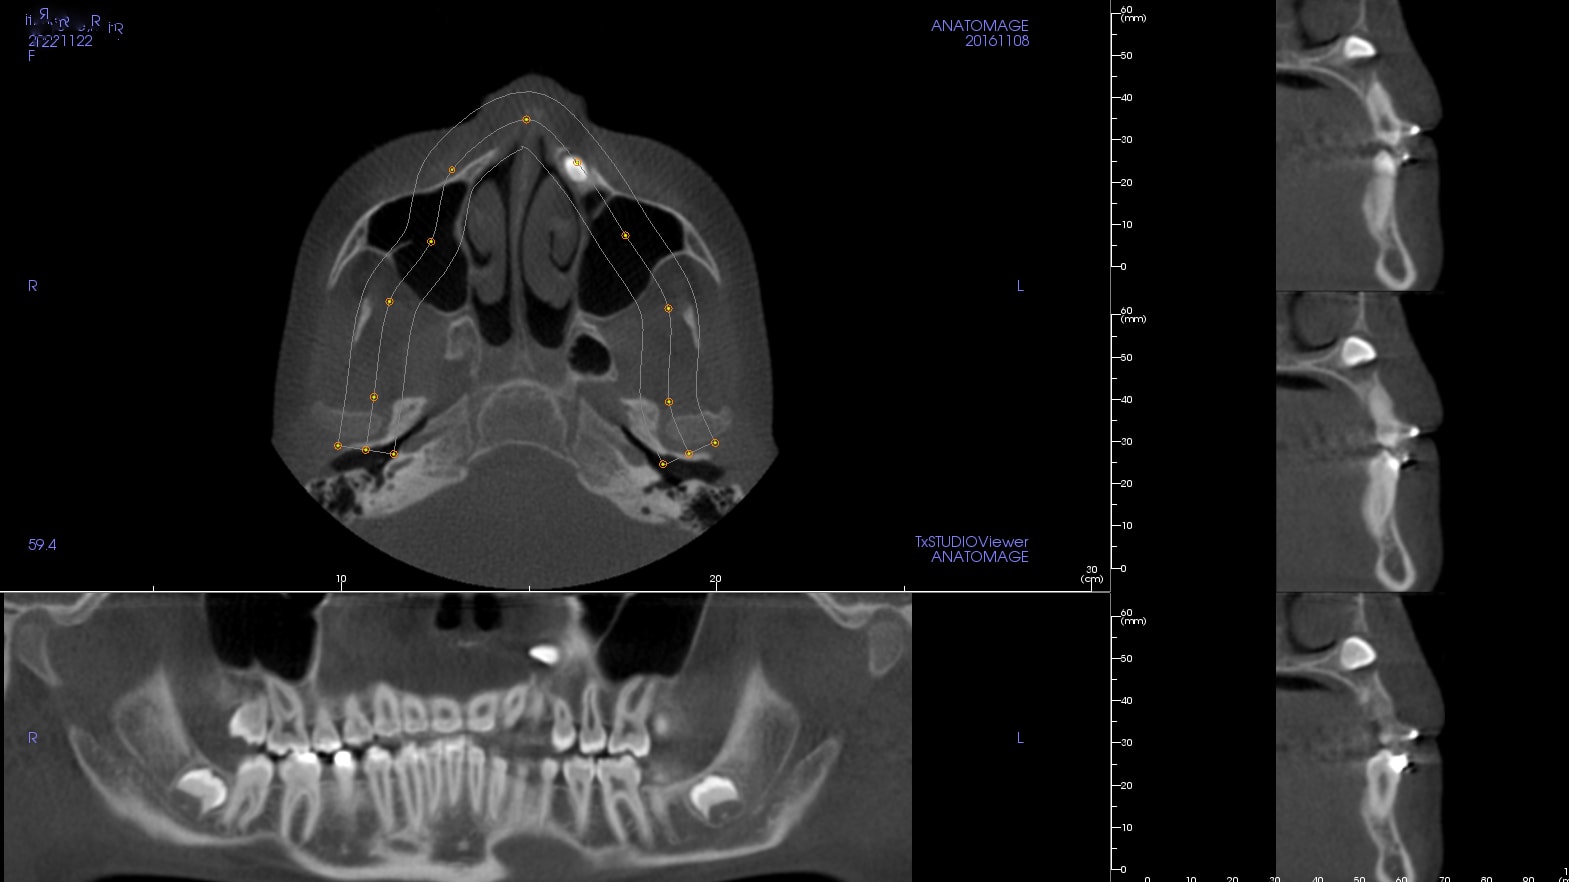

Cette patiente de 13 ans est baguée par un ami orthodontiste depuis un an. Les arcades sont harmonieuses et grosso-modo alignées, la classe 1 se présente bien, et il va falloir désormais s'atteler au principal souci de ce cas ; la 23 incluse.

Comme vous le voyez sur les images issues de la 3D, la 23 est très haute et horizontale.

Là, à la palpation, je sens vaguement la pointe et elle est vraiment sous la fosse nasale. La 3D montre qu'elle est même en gros 1,5mm au dessus de l'apex de la canine lactéale.

Pour une canine haute elle est plutôt bien placée dans la mesure où elle est parallèle au plan sagittal médian => les racines des dents adjacentes ne feront pas trop obstacle au trajet de la traction.